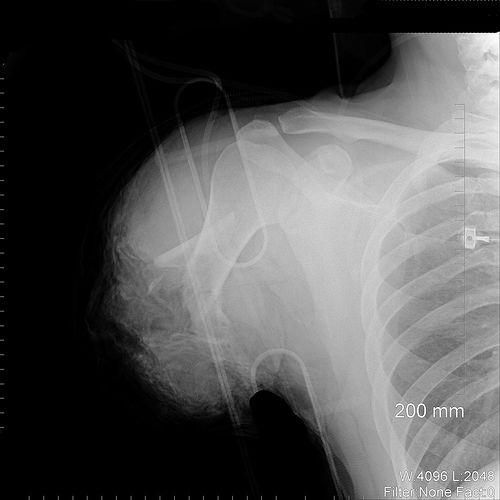

Взрыв петарды в руке ребёнка

Промышленная травма. Ампутация руки.